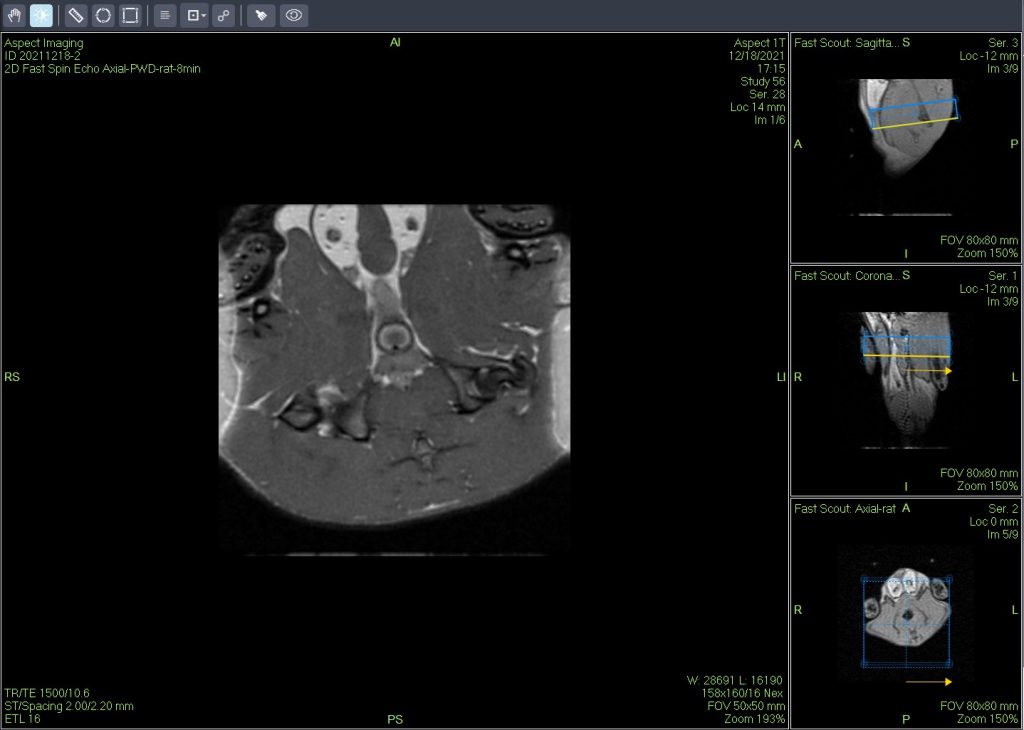

活體磁共振成像在模型小鼠中檢測到局灶性肝損傷(圖A)。肝臟的高分辨率離體MRH評估可以在小鼠(圖B和C)中鑒定幾個單獨(dú)的局灶性脂肪病變。通過常規(guī)組織病理學(xué)證實(shí)病變?yōu)榫衷钚灾靖淖儯▓DC)。